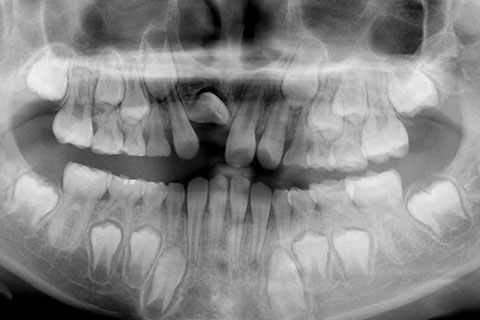

子供の乳歯が抜けて、かなりの時間が経つのに永久歯が生えてこないと心配して来院される親御様は多くいらっしゃいます。この場合、レントゲンにて確認すると大体の場合、もうしばらく待っていれば生えてくるであろうと予測がつきます。しかし、稀に歯の位置異常により、埋まったままの状態で生えてこないことがあります。この場合、待っていても生えてきませんので、矯正力により歯を引っ張り出す必要があります。これを矯正学では開窓・牽引術と呼び、歯肉を切開して、歯の表面を露出させ、そこに矯正器具を付けて、良好な位置まで引っ張り出すという治療法です。